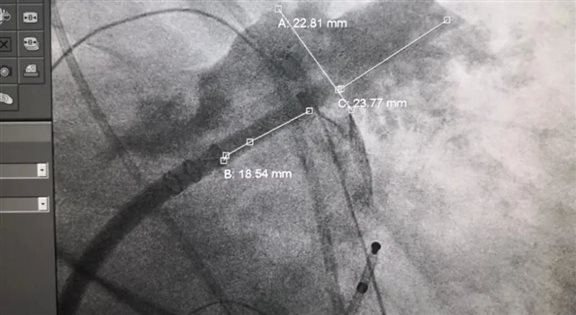

手术在漯河市中心医院心血管内科刘东亮副院长带领下,在超声科、介入科等相关科室的配合下完成。首先,在AI指导下行房颤射频消融术,术中房颤即打停,恢复窦性心律。然后,进行左心耳造影,造影示左心耳鸡翅型,经过详细测量,选用合适的左心耳封堵器,封堵器释放后造影示无残余漏,牵拉试验示封堵器牢固稳定,术中食道超声心动图示封堵器位置良好、无分流。患者各项生命体征平稳,顺利返回病房。